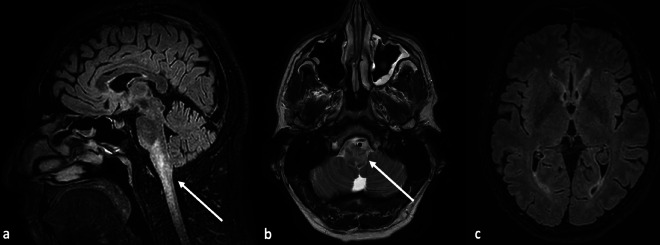

Neuroimaging in PRES: Isolated Brainstem and Spinal Cord Involvement Secondary to Aorto-Iliac Occlusive Disease-A Unique Case Report.

Teaching point: Consider atypical PRES and a vascular work-up in brainstem edema, especially in the setting of severe hypertension.